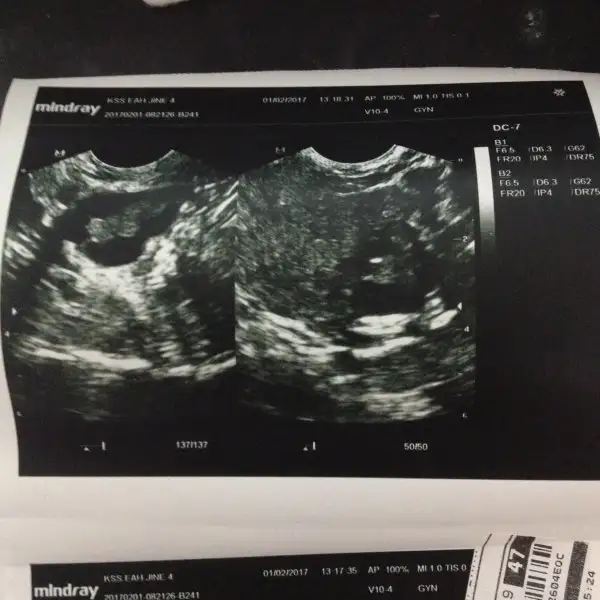

Dün doktora yumurtam varmı diye sordugumda siz polikistik oversınız dedi sasırdım ben gebelik düşünüyordum kızıma kardeş baya üzüldüm sag sol dolmus dedi bana regl gelmeyebilir dedi çeşitli testler istedi ama regl 3.günü olması lazımmıs ama dün akşam benden yumurta akı gibi akıntı geldi ki adetımın belirli zamanlarında gelio ben yumurtluorum sanıodum. Bu sabahta geldi dün regl 14.günü idi acaba dedim ama pko beni durduruyordu dün üzüntüden bişide olmadı aramızda resimleri ekliyorum anlayan birileri pko olan arkadaşlarım varsa banada yardım edebilir mi ?